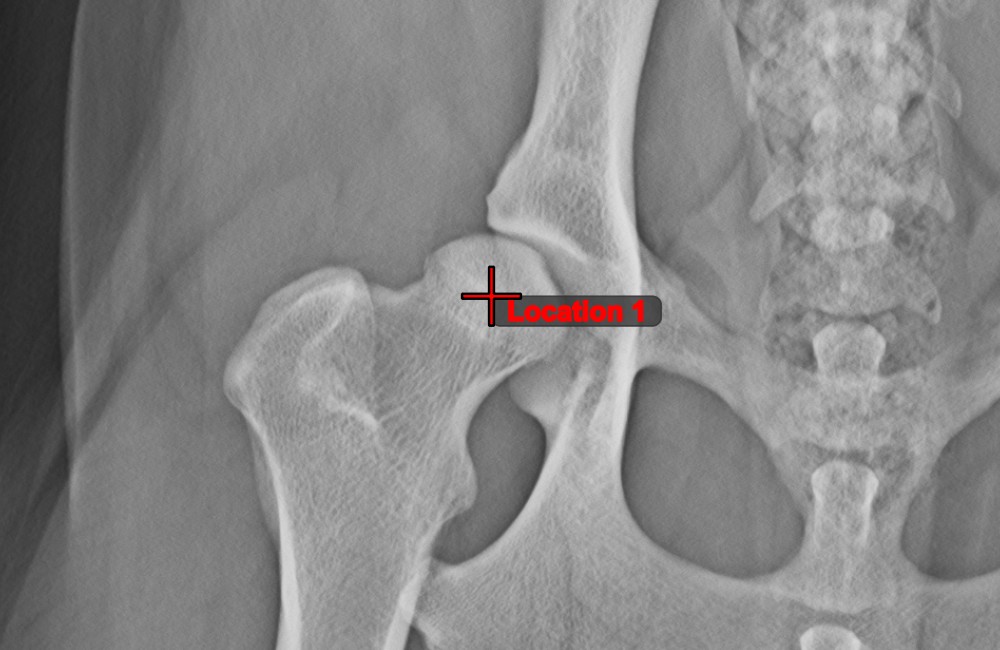

Messpunkt¶

Measurement Point. Jeder Punkt ist zur besseren Identifizierung mit einem Buchstaben versehen.Objekt auswählen/verschieben. Wählen Sie den Punkt mit der zugewiesenen Maustaste des Werkzeugs aus und verschieben Sie ihn dann frei an eine beliebige Stelle im Bild.